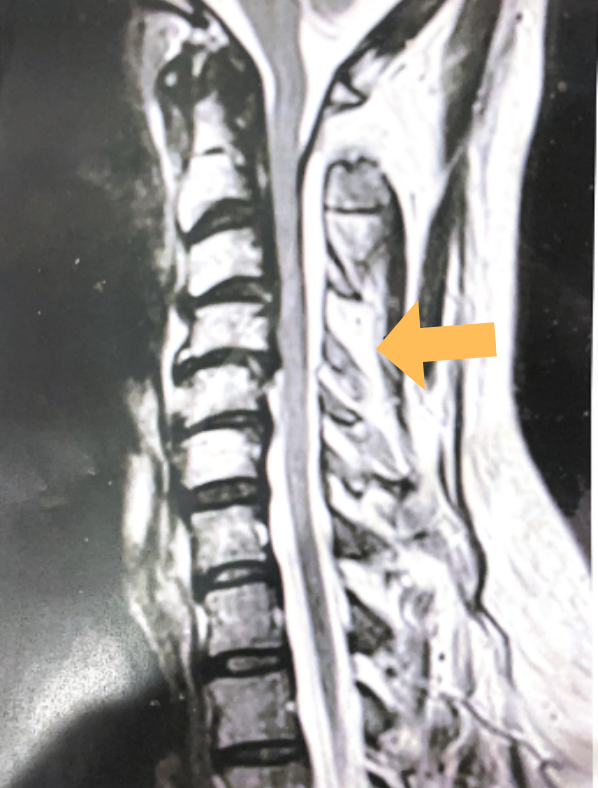

(1b) Hyperintense signal (arrow) at the C3-4 interspinous space consistent with ruptured interspinous ligament,C4-5 (Fig. 1a and 1b).

The fluid was possibly consistent with CSF versus chronic hematoma. The patient was also noted to have a high signal within the interspinous space of C3-C4. This high signal was consistent with a ruptured C3-4 interspinous ligament. Cervical flexion-extension x-rays demonstrated 6 mm of widening of the C3-4 interspinous space on flexion x-ray consistent with cervical instability (Fig. 2a and 2b).

It was felt that the patient was unstable and the patient had signs of early cervical myelopathy secondary to spinal cord compression. The patient consented to undergo exploration and evacuation of the collection and to decompress and stabilize the cervical spine. Upon laminectomy we noticed a ruptured C3-4 interspinous ligament that was consistent with the preoperative imaging studies. After revealing the epidural space during the laminectomy, a large dorsal membrane or pseudomeningocele was noted above a clear fluid collection that was posterior to the dura that was compressing the spinal cord. This membrane was fenestrated and we evacuated the collection which was consistent with CSF. Also during the course of the laminectomy we noted that the source of the CSF leak to be on the left at the takeoff of the C4 nerve root for which the dural sleeve was “degloved” but the fascicles were intact. We repaired with muscle and dural sealants. We completed a C2-C7 laminectomy. The patient had an additional fusion C3-C6 with segmental instrumentation to prevent kyphotic deformity.